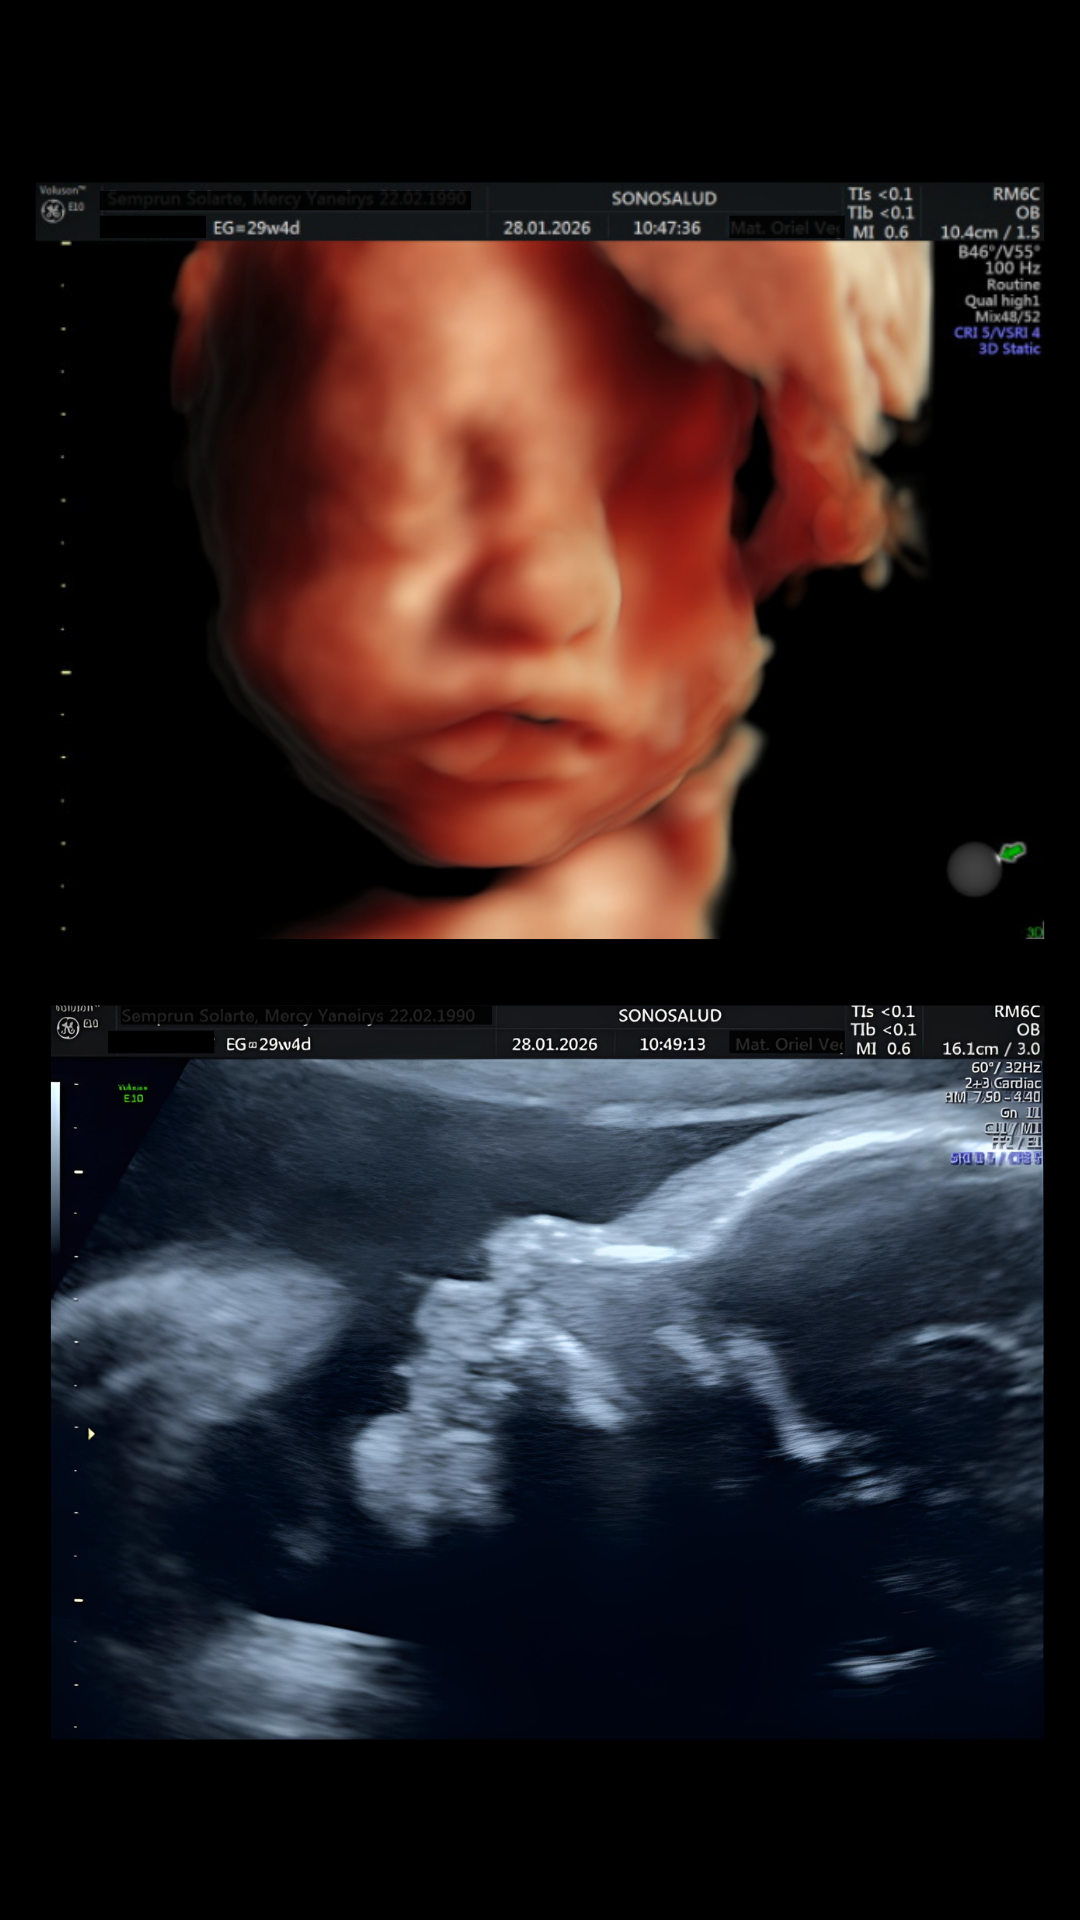

En SonoSalud realizamos estudios ecográficos profesionales con enfoque clínico y alta resolución, utilizando ecografías 5D, obstétricas, ginecológicas y Doppler para entregar información precisa en cada etapa del embarazo y la salud femenina. Nuestras imágenes permiten observar con claridad rasgos, movimientos, estructuras y parámetros materno-fetales, combinando realismo avanzado con criterios técnicos que mejoran la interpretación y confiabilidad de cada examen.

Trabajamos con tecnología Voluson E10, líder mundial en imagenología obstétrica y ginecológica, que ofrece mayor nitidez, contraste y definición de tejidos para una evaluación detallada y diagnóstica. Gracias a esta plataforma y a la experiencia de nuestros especialistas, aseguramos estudios de alta calidad, detección oportuna de hallazgos, mediciones precisas y una experiencia segura y profesional para pacientes y familias.

Así se ve una ecografía 5D en SonoSalud